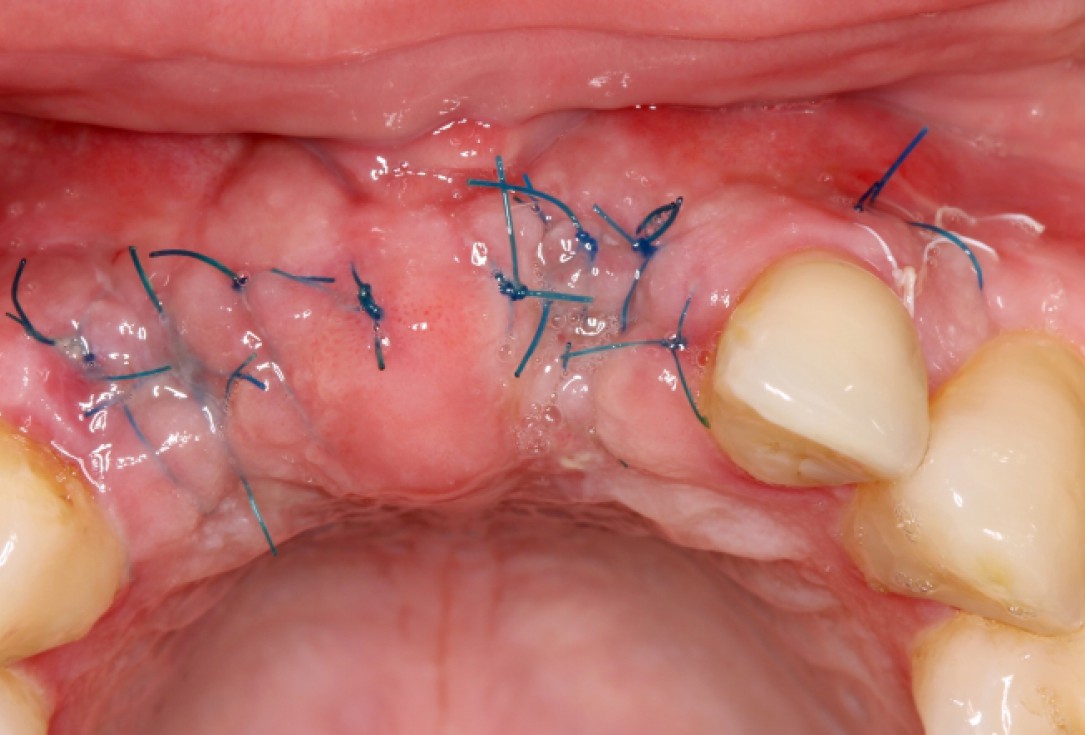

GBR and soft tissue augmentation with cerabone® and mucoderm® - H. Maghaireh & V. Ivancheva

Initial situation: missing teeth #11 & 12 and badly broken #21 root